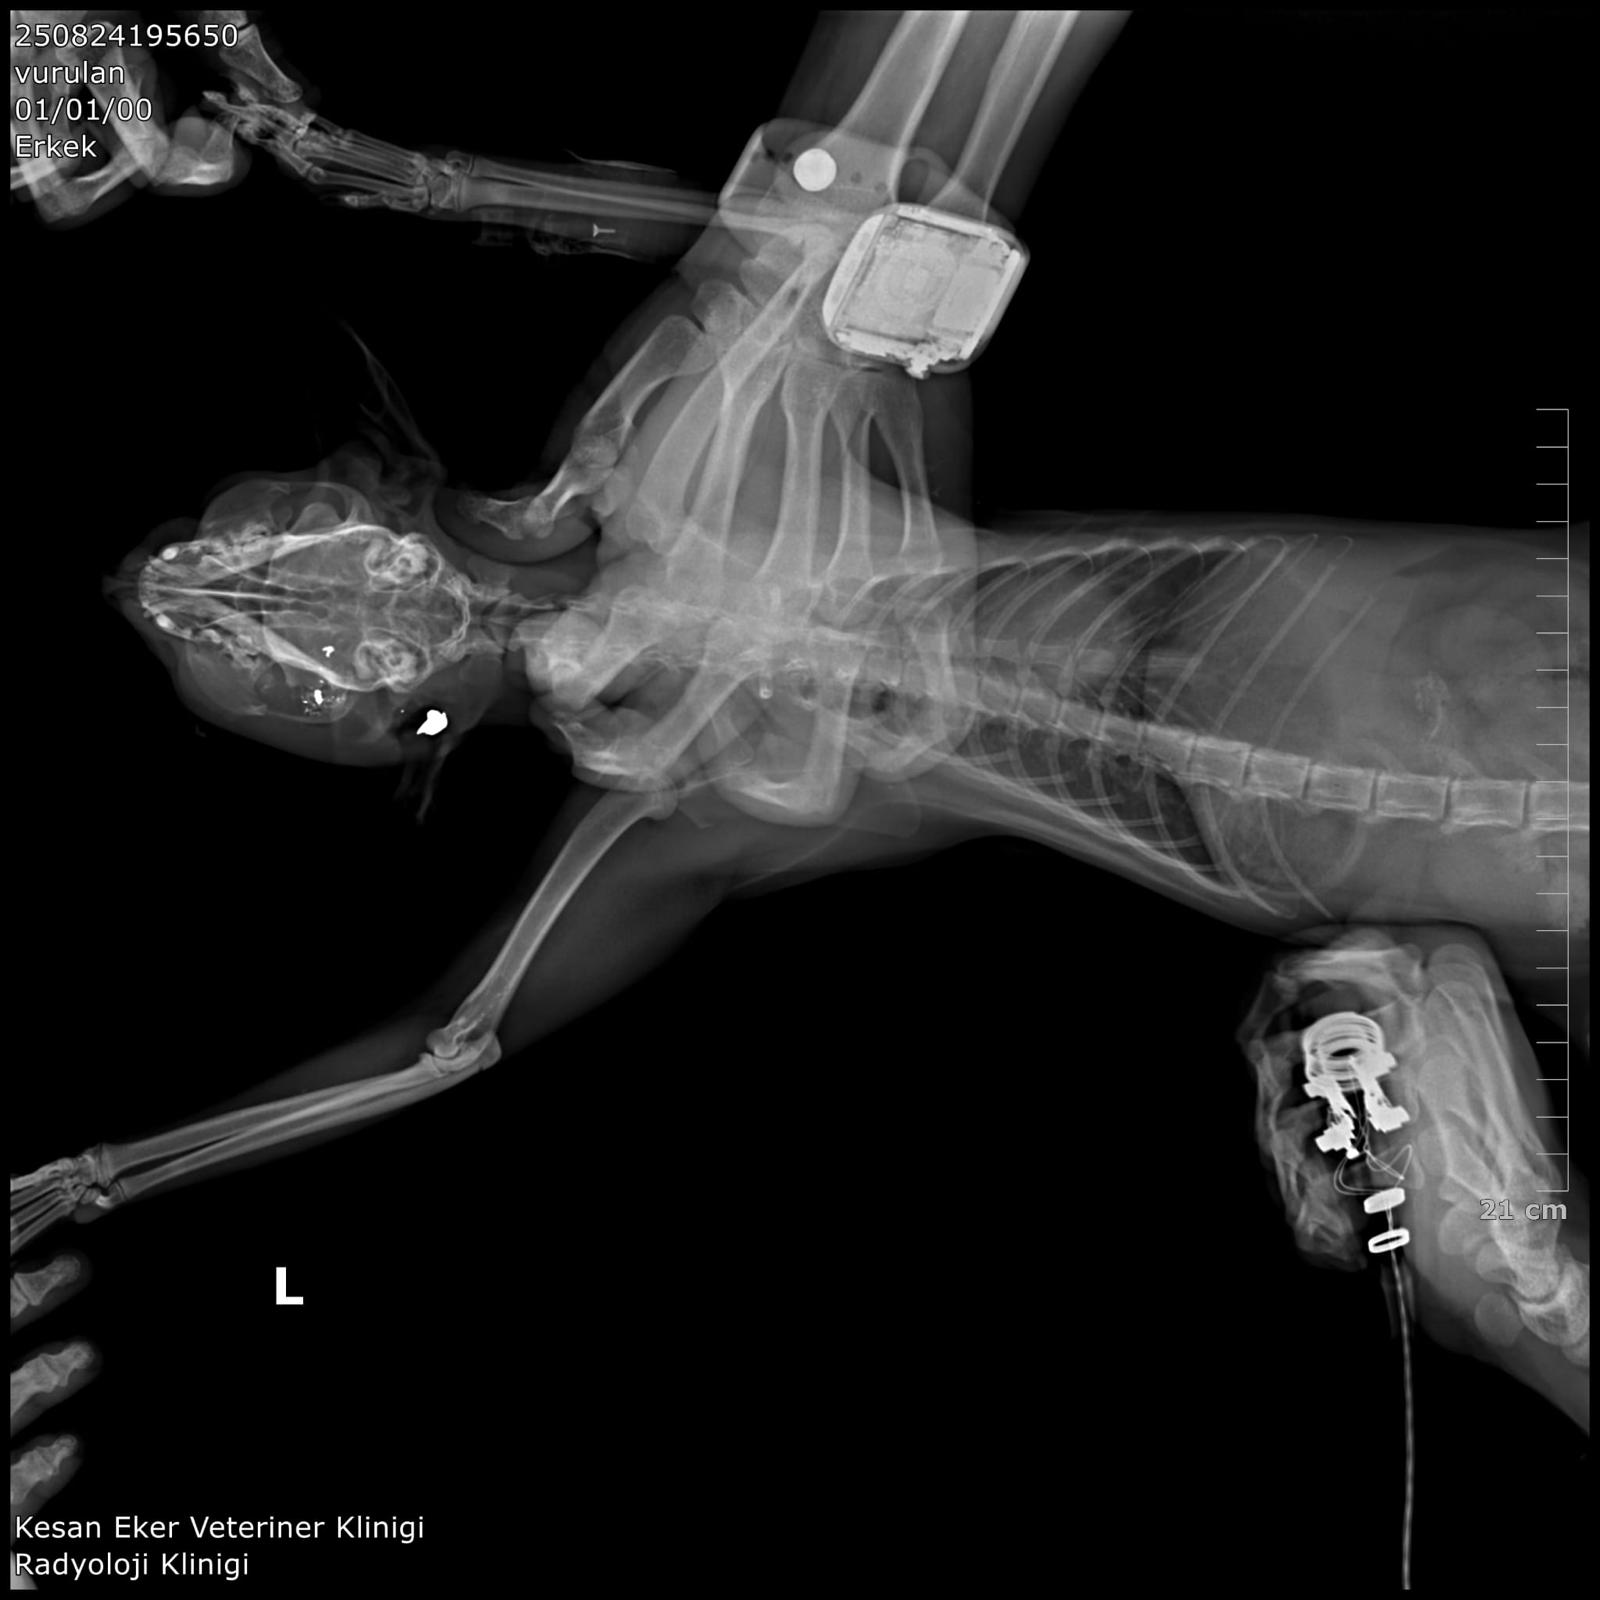

İpsala Cumhuriyet Başsavcılığı'nın olaya ilişkin hazırladığı iddianamede K.G., hakkında, 'Bir ev hayvanını veya evcil hayvanı kasten öldürme' suçundan 6 aydan 3 yıla kadar hapis cezası istendi. İddianamede, "Herhangi bir silah ateşleme görüntüsü tespit edilmese de şüphelinin ikamet ettiği evin bahçe kapısı önünde bir kedinin can çekiştiği ve bir kedinin de kaçtığının tespit edildiği, dosya kapsamında tanık olarak beyanı alınan S.Ç.'nin şüphelinin bahçe kapısı önünde bir kediyi yatar vaziyette gördüğünü, başını sevmek istediğinde kedinin ölü olduğunu fark ettiğini, kediyi eline aldığında başından kan aktığını görmesi üzerine yol üzerinde kalmaması amacıyla kediyi çöp tenekesinin içerisine bıraktığını, ölen ve yaralanan 2 kedi hakkında düzenlenen 25/08/2025 tarihli veteriner hekim ön muayene raporu ile çekilen radyografilerde ateşli silah yaralanması (kuş saçması) ile uyumlu patolojiler gözlemlendiği şeklinde rapor tanzim edildi. Tüm dosya kapsamı incelenmekle şüpheli savunması, bilgi sahibi beyanları, İpsala İlçe Tarım Müdürlüğü'nün yazılı başvurusu, müşteki beyanı, kamera görüntüleri ve kriminal raporları birlikte değerlendirildiğinde, şüphelinin olay tarihinde müşteki Hüseyin Bülbül tarafından da beslenmekte olan sokak kedilerine ateş etmek suretiyle, bir kedinin ölümüne neden olarak üzerine atılı suçu işlediğine dair ve bir kedinin yaralanmasına neden olarak tariflenen suçu işlediğine dair hakkında kamu davası açmak üzere yeterli şüphe oluşturacak kadar delilin mevcut olduğu anlaşılmakla" denildi.